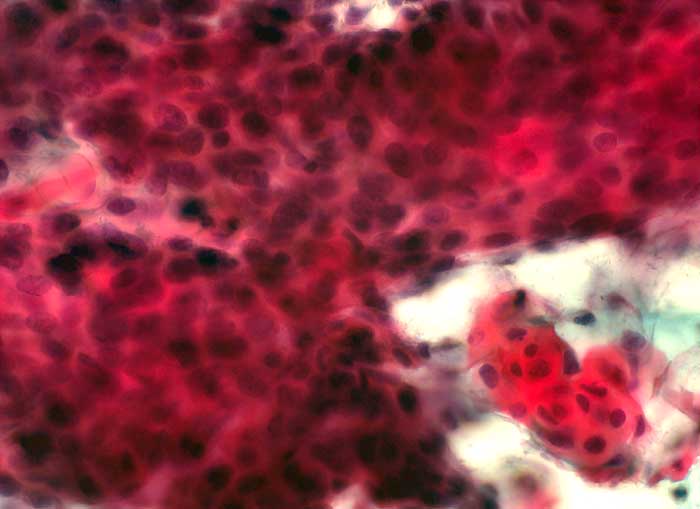

PathoPic – image database / PathoPic ID 6207 - verhornende schwere Dysplasie HSIL

verhornende schwere Dysplasie HSIL

Portioabstrich: teils hochgradig-atypische Plattenepithelien mit unterschiedlich grossen, teils polymorphen, hyperchromatischen und grob strukturierten Kernen. Zahlreiche Zellen mit hellorangem, verhorntem Zytoplasma und teilweise hyperchromatischen und geschrumpften Kernen.

Verdacht Kondylom an der Portio.

Zytologie

400